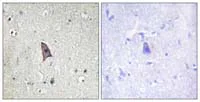

Immunohistochemistry (Formalin/PFA-fixed paraffin-embedded sections) - Anti-TIE2 (phospho Y1102) antibody (AB111585)

Immunohistochemistry analysis of (phospho Y1102) in paraffin embedded Human brain tissue, using ab111585 at a 1/50 dilution. The image on the right is treated with the synthesized peptide.